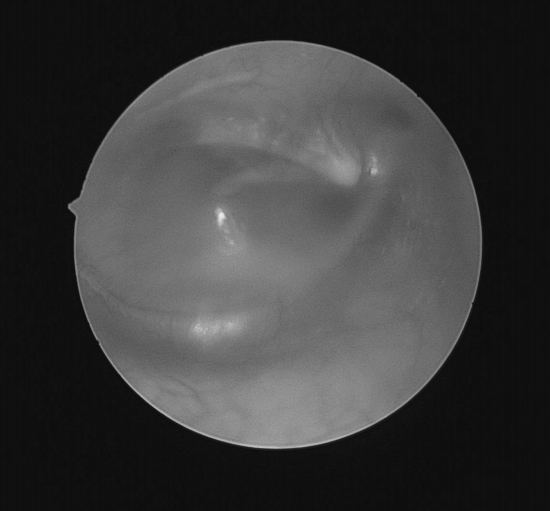

耳内镜检查:分泌性中耳炎(右)

双耳鼓膜完整,右侧鼓膜内陷明显,右侧鼓室可见积液